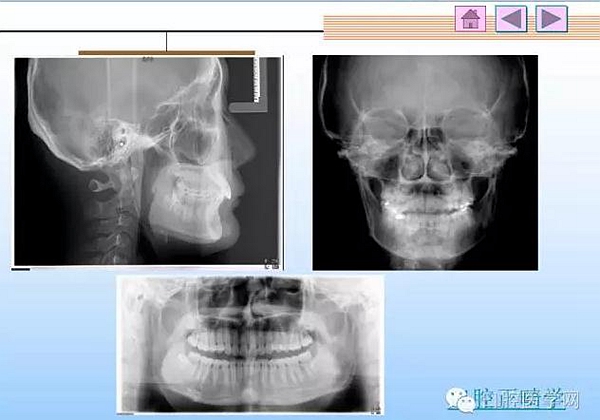

口腔正畸學病歷書寫:歷來臨床的病歷書寫都是一個普遍而又實際困難的地方,尤其是口腔正畸學,很難有規(guī)范的書寫格式,在這里,把我精心保存的病歷書寫用幻燈的格式傳給大家,便于觀看,從教學到臨床都有很好的指導作用。